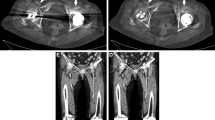

Altogether 85 DSA and corresponding DVA image pairs (Fig. 2) were compared directly using the online questionnaire to evaluate the image quality and the diagnostic benefit. The overall preference of DVA was observed in 84.5% of all images; the interrater agreement for all comparisons was 83.2% with a Fleiss κ value of 0.454 and p < 0.001 (Table 3, Fig. 3). With regard to the specific questions (details, diagnostic value, therapeutic decisions), the DVA preference was slightly higher in the implant-free images (quality agreement 86.7–90.4%, interrater agreement 88.1–89.6%, Fleiss κ 0.404–0.487, p < 0.001 in all cases, Table 3) than in the implant-containing images (quality agreement 79.2–84.2%, interrater agreement 76.7–81.7%, Fleiss κ 0.239–0.408, p < 0.005 in all cases). DVA was preferred in 83.75% of comparisons in terms of image quality in the vicinity of implants with a 79.6% interrater agreement and Fleiss κ 0.454 with p < 0.001 (Table 3).

Paired comparison of DVA and DSA images. The bar graph indicates the preference of DSA & DVA images. The numbers below bars represent the different question types (1: details, 2: diagnostic value, 3: ease of therapeutic decisions, 4: blood vessel visibility around the implant). Major gridline unit was changed from 20 to 10 in the upper graph. DSA: digital subtraction angiography; DVA: digital variance angiography